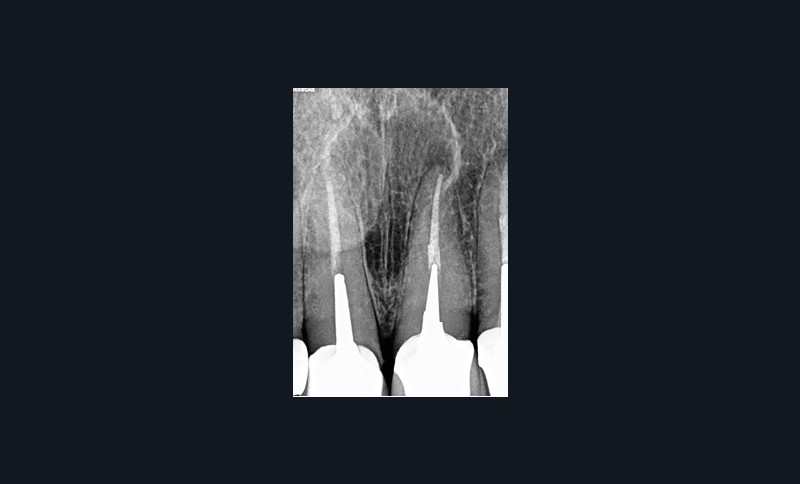

Lors de la consultation en endodontie, l’interrogatoire et l’examen clinique sont prépondérants dans l’établissement du diagnostic. Celui-ci nécessite la plupart du temps la prise de clichés radiographiques. Selon la Haute Autorité de Santé, la radiographie rétro-alvéolaire est même un prérequis obligatoire à tout traitement endodontique. Cependant, les résultats des tests cliniques, tout comme l’analyse sur radiographie rétro-alvéolaire, peuvent être subjectifs. Le CBCT pallie en partie ces limites par une analyse tridimensionnelle de l’anatomie canalaire et de ses rapports avec le milieu extra-radiculaire, permettant d’affiner le diagnostic. Il permet de détecter 60,9 % des radio-clartés péri-apicales, contre seulement 39,5 % avec une radiographie rétro-alvéolaire [2]. Cette aide au diagnostic explique pourquoi les endodontistes interrogés modifiaient leur diagnostic étiologique dans 55 % des cas présentés et leur prise en charge dans 49 % des cas lorsqu’ils avaient accès au CBCT [3]. On comprend alors qu’en cas d’incertitude ou face à une anatomie canalaire complexe, la Société Européenne d’Endodontie et l’Association Américaine d’Endodontie recommandent de réaliser un examen complémentaire 3D afin d’éviter toute perte de chance pour le patient. Cela est particulièrement pertinent pour affiner le diagnostic et retrouver une dent causale lorsque le diagnostic étiologique est compliqué (fig. 1) ainsi que pour exclure une pathologie d’origine non endodontique (fig. 2).